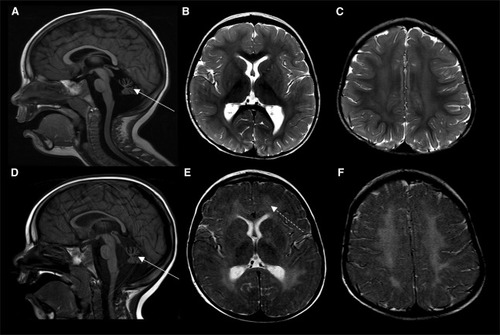

MRI characteristics of individual 1 Brain MRI of individual 1 at 17 months (A–C) and 35 months of age (D–F). (A) and (D) Sagittal T1-weighted images at the midline showing cerebellar hypoplasia (thin arrows). (B, C, E, and F) Axial T2-weighted images at the level of the basal ganglia (B and E) and centrum semiovale (C and F) showing progressive diffuse demyelination (dotted arrow).  |